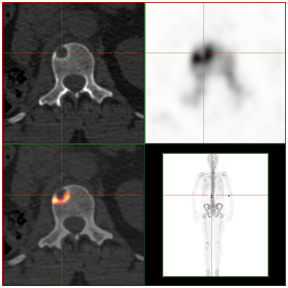

骨转移图片三维图片,骨转移图片

骨转移瘤的影像诊断

肺癌骨转移骨扫描图片

骨扫描显示骨转移图片

肺癌骨转移ct图片

骨扫描骨转移